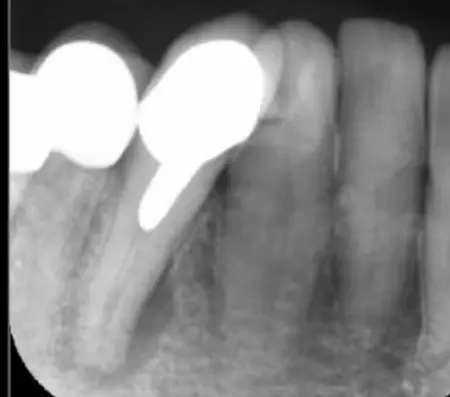

治療前

治療後

レントゲンを撮影して詳しく拝見したところ、痛みが出ている右下前歯の根の周囲には黒い影が見られました。この影は、歯の内部に細菌が侵入して炎症を起こし、歯根の先に膿が溜まる「根尖(こんせん)病変」によるものです。

この歯は以前、細菌感染した神経を取り除き、神経が入っていた細い管「根管」を清掃して薬を詰める「根管治療」を行っていました。根管治療後には被せ物が装着されていましたが、その被せ物が経年劣化した、もしくは根管治療が不十分だったことが原因で、再度細菌が根管内に侵入して炎症を起こしたと考えられます。

まずは装着されている古い被せ物を外し、唾液に含まれる細菌や血が根管内に入るのを防ぐために、ゴム製のシート「ラバーダム」で覆って治療部位だけを露出させます。次にマイクロスコープで確認しながら、感染した部位を丁寧に除去しました。

根管内が清潔になったことを確認し、再び細菌が入り込まないようしっかりと薬を詰めました。

その後は最終的な被せ物を作製するために、歯の形を整えてから型取りを行います。後日、完成したジルコニアクラウンを装着し、噛み合わせに問題がないかをしっかりと確認しました。

治療後は、経過観察のために3ヶ月後と6ヶ月後にレントゲンやCTの撮影をしたところ、歯根周辺にあった根尖病変の影が徐々に小さくなり、歯を支える骨が再生してきていることが確認できたため、治療を終了しています。